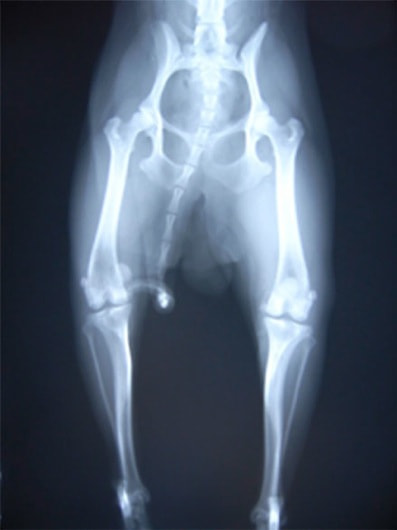

内方膝蓋骨脱臼の発生原因は内反股と大腿骨頸の前捻であると結論づけている研究があります。また、遺伝的要素が重要と考えられており、大腿四頭筋機構の異常、股関節異常、後肢の変形との関連などが報告されておりますが、現在でも正確な病因あるいは発生機序は分っておらず、治療方針や合併症の問題に関して議論が続いています。10kg以下の小型犬に多く認められる傾向があること、大型犬でも内方への脱臼が全体の75~90%を占める傾向があります。

時々肢を挙上する間欠的な歩行異常が多く、常に肢を挙上するケースは少ないです。肢を後ろに伸ばす動作を繰り返し、それを主訴に来院されることもあります。日常生活において膝蓋骨の脱臼と整復を繰り返し、関節軟骨が磨耗すると症状は悪化し、歩行異常はより顕著化します。更に四頭筋機構が関節を安定化させられなくなることも手伝い、前十字靭帯断裂症が併発することもあります。